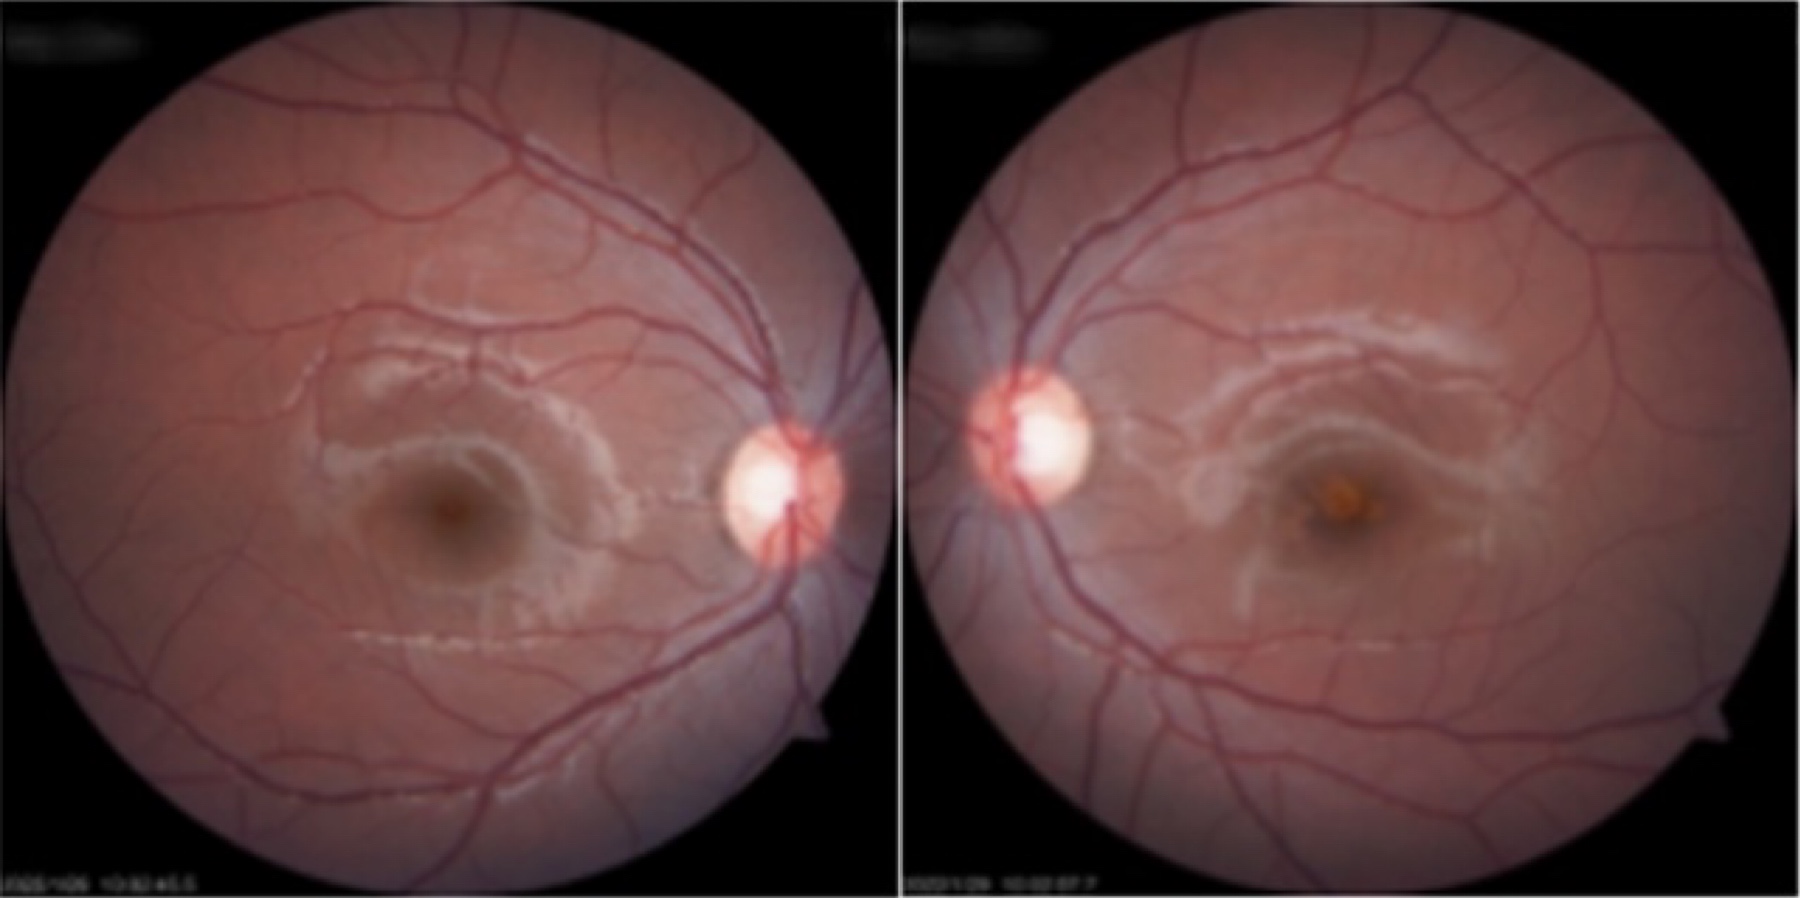

为了明确黄斑部病变性质,彭鸿钧教授给小董进一步做了视网膜的光学相干断层成像检查(OCT检查),这个检查可以很精确显示视网膜各层结构和感光细胞的情况,精确判断视网膜的病变。OCT检查结果显示,小董左眼黄斑区中央可见病灶处外层视网膜断裂,感光细胞受损。

OCT检查:正常的黄斑部(左)黄斑部外层视网膜缺失(右)

小董的左眼是典型的视网膜激光损伤。很遗憾的是,激光的损伤已经造成了小董视网膜视细胞不可逆的损伤。以目前的医学水平,左眼的视力下降是不可恢复的。